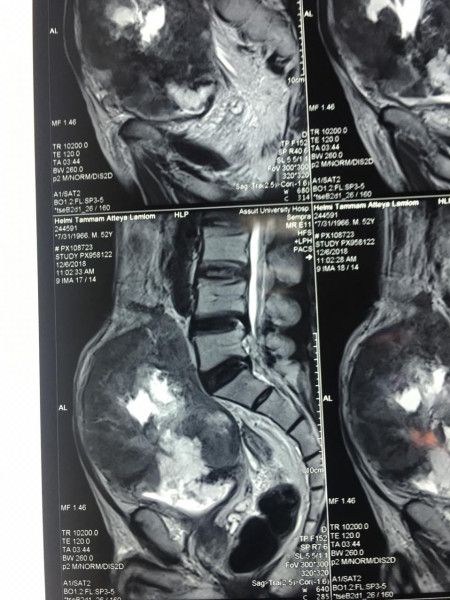

كما كشف الدكتور عمرو أبو فدان المدرس بقسم جراحة المسالك وعضو الفريق الطبي المسئول عن العملية انه فور وصول المريض إلى المستشفى تم خضوعه لعدد من الإشاعات والفحوصات الأولية والتي بينت تضخم حجم الورم مما يستلزم التدخل الجراحي لفصل الورم عن الأنسجة المحيطة وإنقاذ حياه المريض وبالفعل تم إجراء الجراحة بنجاح وخرج المريض من غرفة العمليات دون أي مضاعفات كما تم متابعة الحالة فى غرفة العناية المركزة لمدة 24 ساعة وعند استقرار حالة المريض تم نقله إلى غرفته بمستشفى جراحة المسالك البولية والكلى.